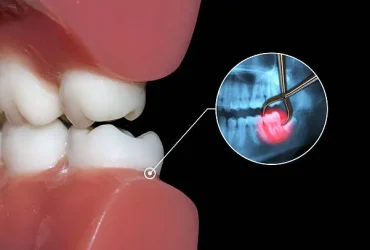

ฟันคุดคือ อะไร

ฟันคุดคือ ฟันกรามซี่ในสุด ทั้งหมด 4 ซี่ บน ล่าง ซ้าย ขวา ไม่สามารถขึ้นได้ตามปกติเพราะพื้นที่ไม่เพียงพอให้ฟันสามารถขึ้นมาได้ บางซี่อาจจะโผล่ขึ้นมาเล็กน้อย และบางซี่ถูกฝั่งอยู่ในกระดูดขากรรไกร อาจจะขึ้นตรง เอียงหรือนอนในแนวราบส่วนใหญ่ฟันคุดมักพบว่าอยู่ที่ฟันกรามซี่ล่างในสุดและพบมากสุดในช่วงอายุ ประมาณ 16 – 25 ปี หรืออาจจะช้ากว่านั้น